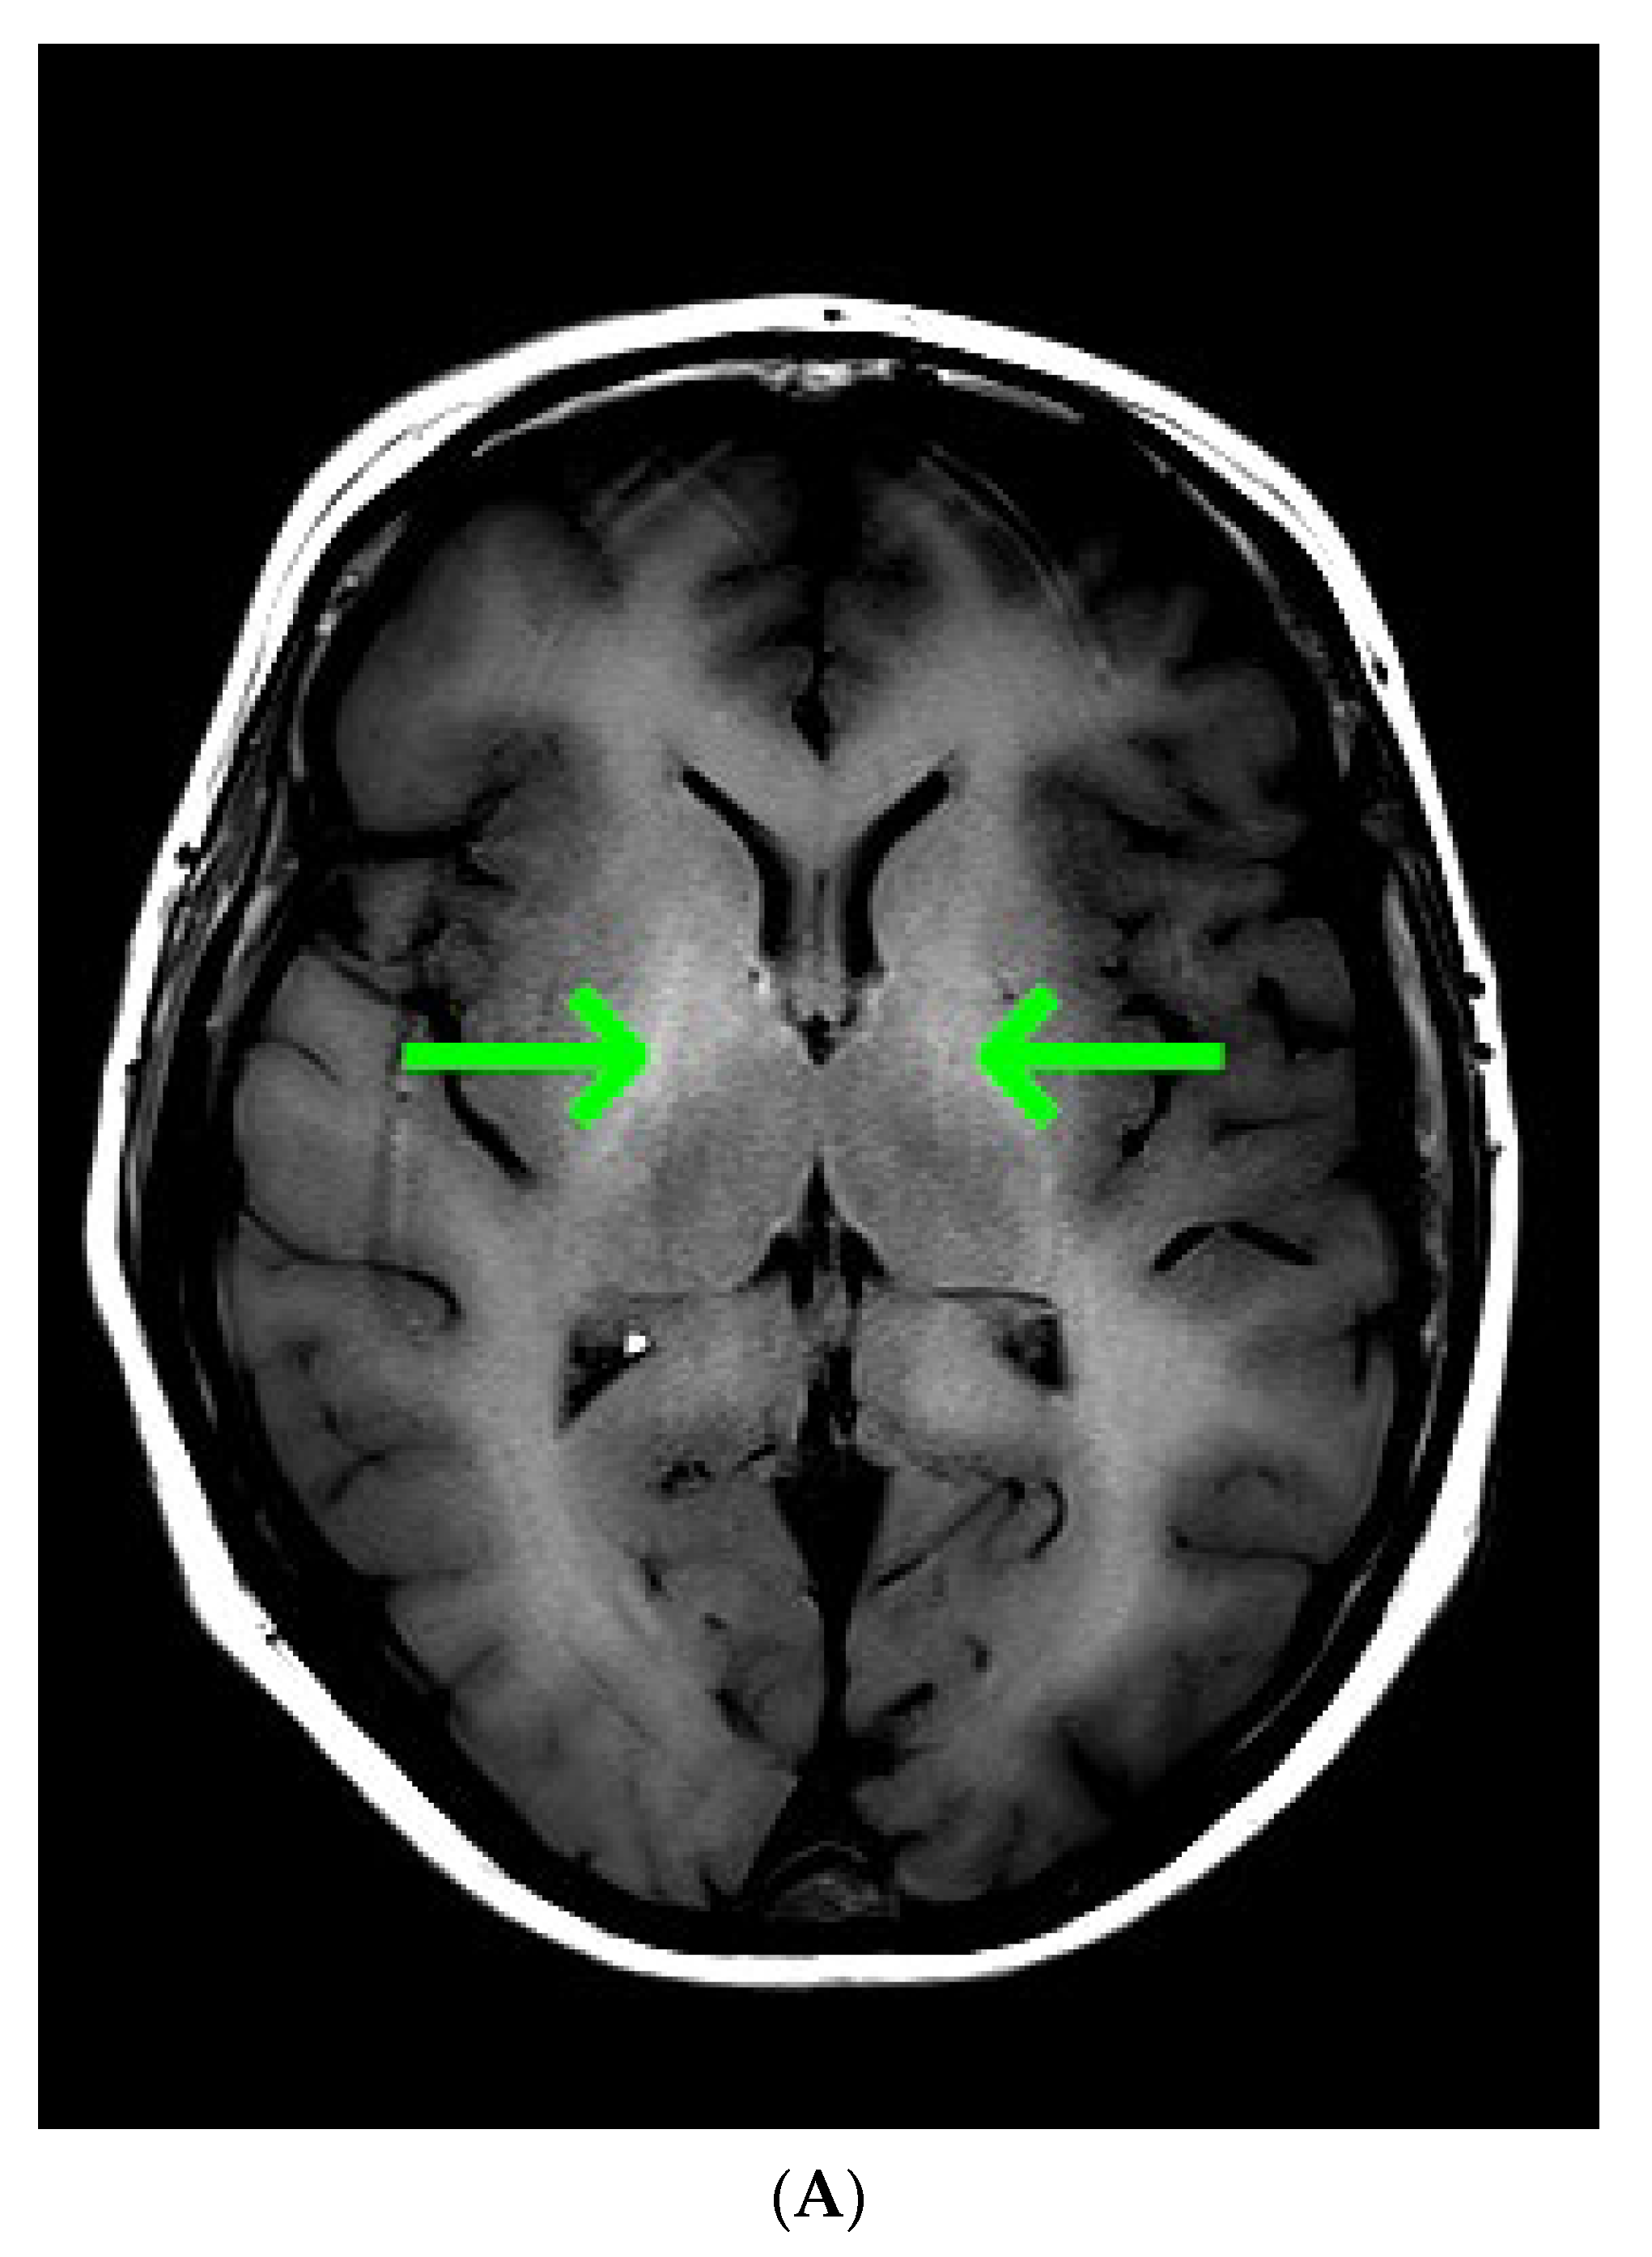

Common causes of decompensation of chronic liver disease include gastrointestinal (GI) bleeding, infection, high alcohol intake and hepatotoxic medications [1]. As the last three were unlikely, urgent esophagogastroduodenoscopy was ordered, however it showed non-bleeding esophageal varices and scarification following previous banding procedures in the middle and lower part of the esophagus. Gastrointestinal bleeding being the most likely cause of chronic liver decompensation was therefore excluded. In order to find the cause of impaired consciousness multimodal diagnostic assessment was initiated. Toxic screen showed absence of phenobarbital, carbamazepine, benzodiazepines, tricyclic antidepressants; valproic acid was present in the subtherapeutic concentration of 41 µg/mL (therapeutic range 50–100 µg/mL). On day 3 of ICU hospitalization angio-CT of the head was performed and also revealed no abnormalities. The EEG showed no signs of epileptiform activity, although generalized inhibition of basal activity was present. The direct chemiluminescence of the cerebrospinal fluid (CSF) performed on day 4 showed absence of IgG and IgM against B. burgdorferii, Herpes simplex virus, and cytomegalovirus. There was no DNA of Ebstein-Barr virus detected in the CSF sample. The onco- and anti-neuronal immunoglobulin panel performed with indirect immunofluorescence was negative: anty-Amp, anty-Cv2.1, anty-PNM2/Ta (Ma2/Ta), anty-Ri, anty-Yo, anty-Hu, anti-Rec, anti-SOX1, anti-titin. The anti-neuronal screen performed with indirect immunofluorescence was negative: anty-AMPA (GluR1/GluR2), anty-GABA B, anty-NMDA, anty-DPPX, anty-CASPR 2, anty-LGl 1). All initial microbiology cultures (blood, aspirate, urine, CSF) were negative. As part of diagnostic assessment the magnetic resonance imaging (MRI) examination of the head was performed on day 5. The image obtained by MRI is depicted in Figure 1A–D.

Figure 1.

(A) Magnetic resonance imaging of the head. T1 Spin Echo, axial. Green arrows point to hyper-intense globi pallidi; (B) Magnetic resonance imaging of the head. T2 Turbo Spin Echo Dark-fluid. Red single arrows point to the mild symmetric hyper-intensity in the insulas; double red arrow point to the pronounced hyper-intensity in the left occipital lobe; (C) Magnetic resonance imaging of the head. Diffusion Weighted Imaging b = 1000, axial. Cyan arrows point to the restricted water diffusion in both thalami; (D) Magnetic resonance imaging of the head. Apparent Diffusion Coefficient, b = 0, b = 1000, axial. Cyan arrows point to the restricted water diffusion in both thalami.

Taking into account clinical picture the differential diagnosis involved: chronic liver encephalopathy, acquired hepatocerebral degeneration (AHD), acute liver encephalopathy. Various nonspecific, not limited to vascular supply region, lesions of the brain, including rare appearance like T1 gray matter hyper-intensity, were consistent with hepatic encephalopathy. Because liver encephalopathy was a possible diagnosis, ammonia concentration was determined. The ammonia concentration determined with spectrophotometry reached 417 µg/dL, highly above the reference range (31–123 µg/dL). Ammonia was found to be an independent risk factor for hepatic encephalopathy and intracranial hypertension, the latter occurring in 55% of patients with ammonia concentrations >200 μmol/L (340.6 µg/dL) [2].